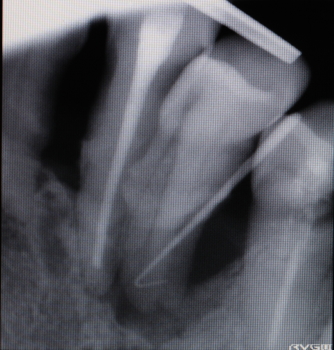

| 2016年07月22日 同部のX-ray 骨の吸収が著しい アクセサリポイントを歯肉溝から挿入すると 根先近くまで入る。 |